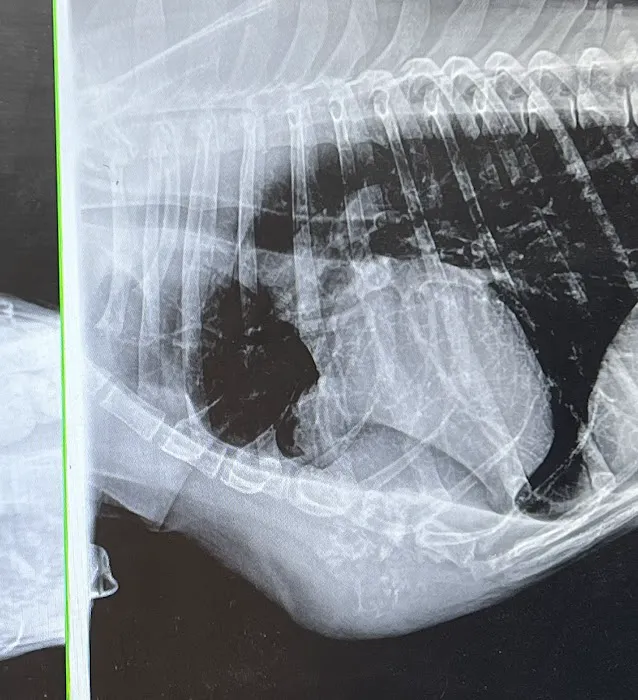

- Wellness & Diagnostics: Blood Work, Diagnostic Radiology, Diagnostic And Treatment, and Health Certificates.

- Diagnostic Radiology